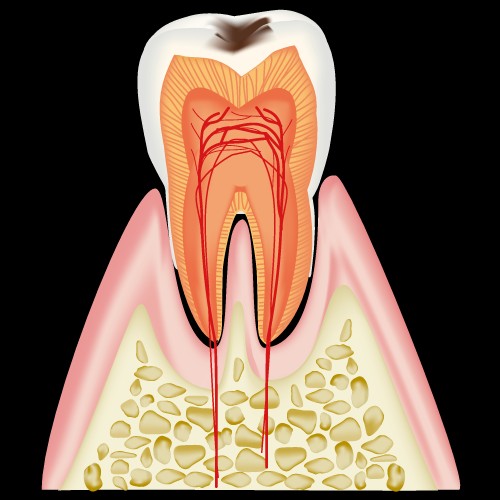

まずは、健康な歯の図です。

歯は三層に別れていて

- エナメル質

- 象牙質

- 歯髄

と呼ばれ、どこまで到達したか、が分類の基準となります。

C0:白濁もしくは着色のある歯

C1:エナメル質が脱灰した初期の虫歯

C2:象牙質まで進行した虫歯

C3:歯髄まで進行した虫歯

C4:歯の根だけが残った状態